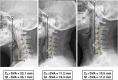

Results: The mean follow-up was 16.86 ± 5.63 and 18.36 ± 7.51 months in the ACDF with UT group and ACDF without UT group, respectively (p > 0.05). The average preoperative VAS arm score was 5.89 ± 1.00 in the ACDF with UT group and 5.18 ± 1.21 in the ACDF without UT group (p = 0.038). However, the average VAS arm score was 4.22 ± 0.64, 4.06 ± 1.13 and 1.68 ± 0.71, 1.60 ± 0.70 at 1 week post operation and at final follow up, respectively, (p > 0.05). We also found that the C2-7 SVA and St-SVA at the last follow-up and their change (last follow-up value - preoperative value) in the ACDF with UT group were significantly higher than ACDF without UT group (p < 0.05). No marked differences in the other cervical sagittal parameters, fusion rate or complications, including dysphagia, ASD, and subsidence, were observed.

Conclusions: Our result indicates that ACDF using a zero-p implant with or without partial UT both provide satisfactory clinical efficacy and acceptable safety. However, additional partial UT may has a negative effect on cervical sagittal alignment.